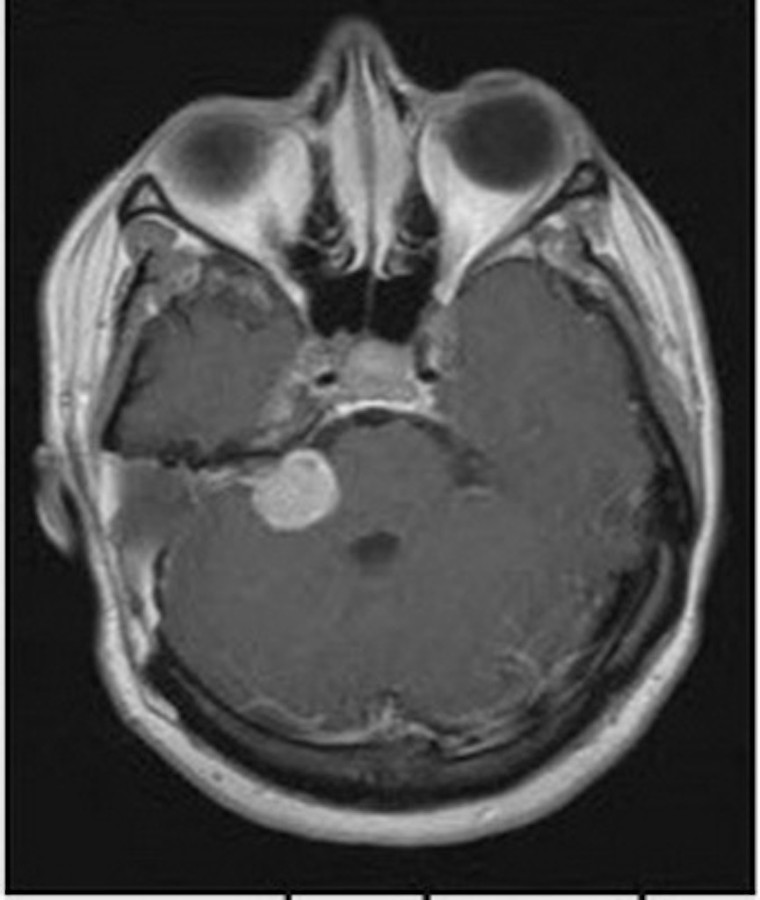

Trong số các nguyên nhân điếc đột ngột, khoảng 0,8 - 4% người bệnh có u ống tai trong hoặc u góc cầu - tiểu não (xem ảnh), ngay cả khi người bệnh đã hồi phục thính lực hoàn toàn cũng không thể hoàn toàn loại trừ các nguyên nhân này. Do đó, chụp cộng hưởng từ (MRI) có tiêm gadolinium là xét nghiệm phù hợp nhất để loại trừ các bệnh lý sau ốc tai. Nếu không thể chụp cộng hưởng từ, người bệnh nên được đo điện thính giác thân não hoặc đo lại thính lực đồ trong quá trình điều trị, các bất thường kéo dài trên 2 xét nghiệm này có thể gợi ý cho các bệnh lý sau ốc tai.

Phát hiện và xử trí sớm điếc đột ngột ảnh 2

Khối u thần kinh tiền đình ở góc cầu - tiểu não gây điếc đột ngột.